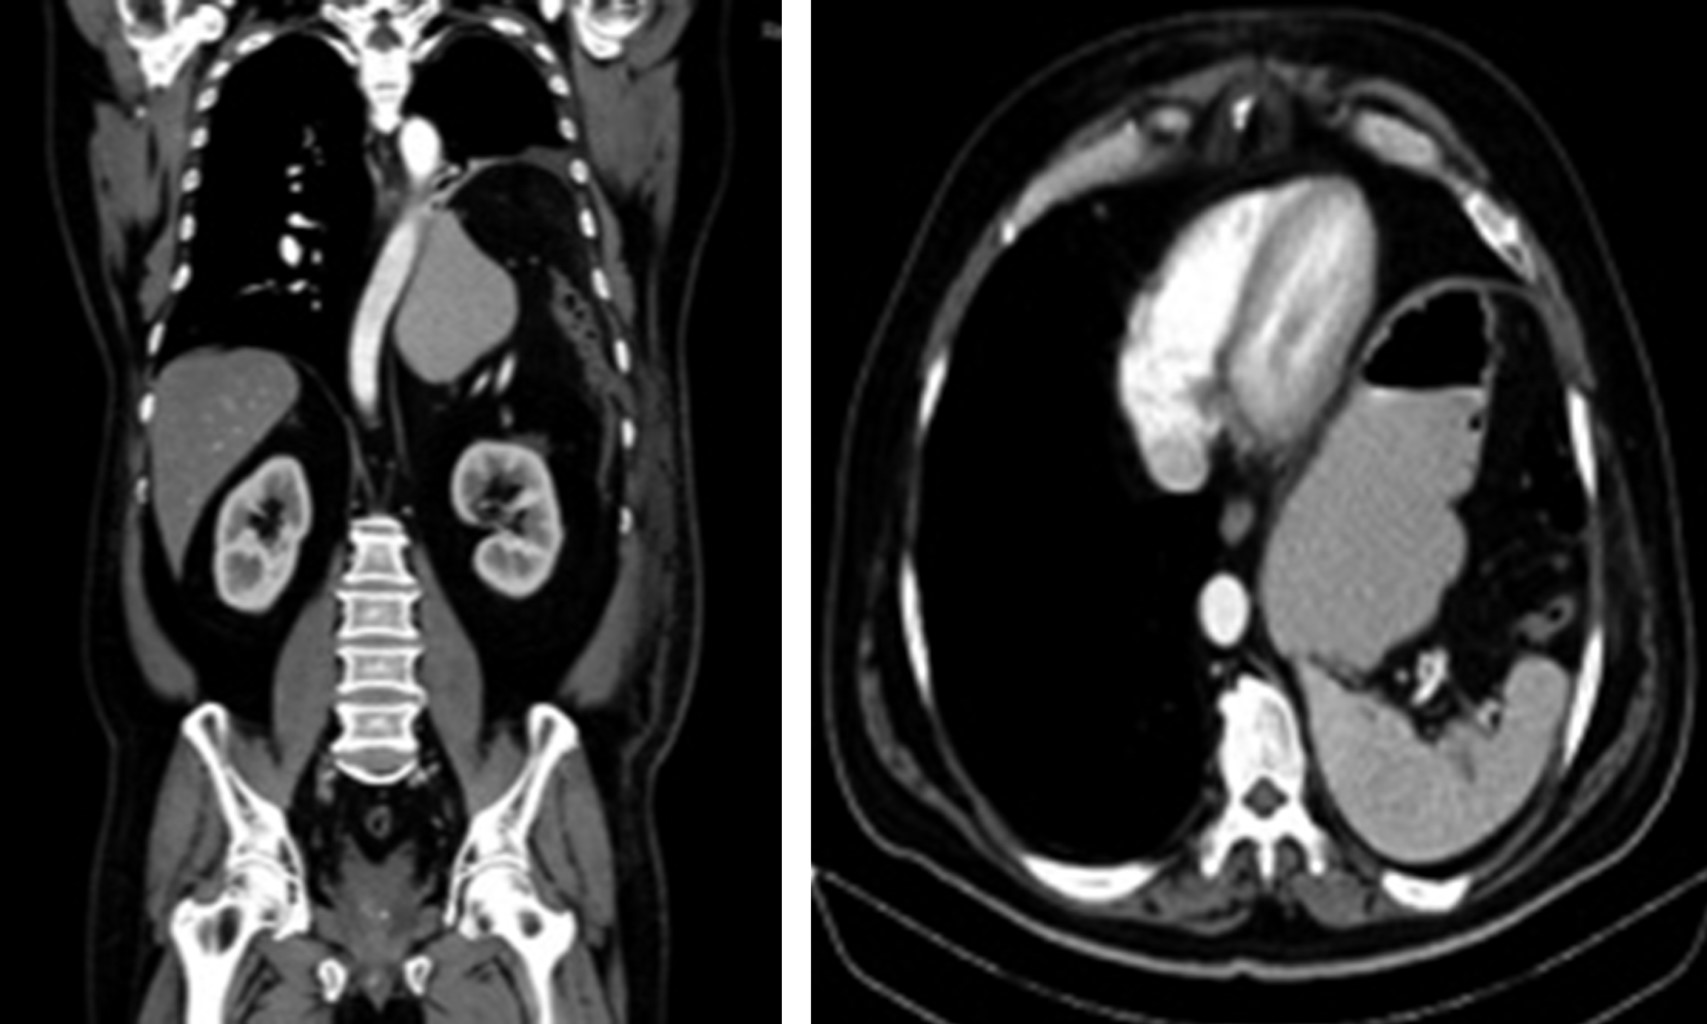

Cursó con distensión abdominal y ausencia de evacuaciones, se realizó radiografía de tórax (Figura 1), la cual mostró disminución del parénquima pulmonar izquierdo por presencia de burbuja aparentemente hidroaérea gástrica; ante estos hallazgos se decidió realizar tomografía de tórax (Figura 2) que reportó nivel hidroaéreo arriba del límite diafragmático izquierdo haciendo un cuello de botella en la continuación del tracto digestivo, además de visualizarse bazo con engrosamiento cicatrizal en la periferia hacia pared torácica.

Figura 2